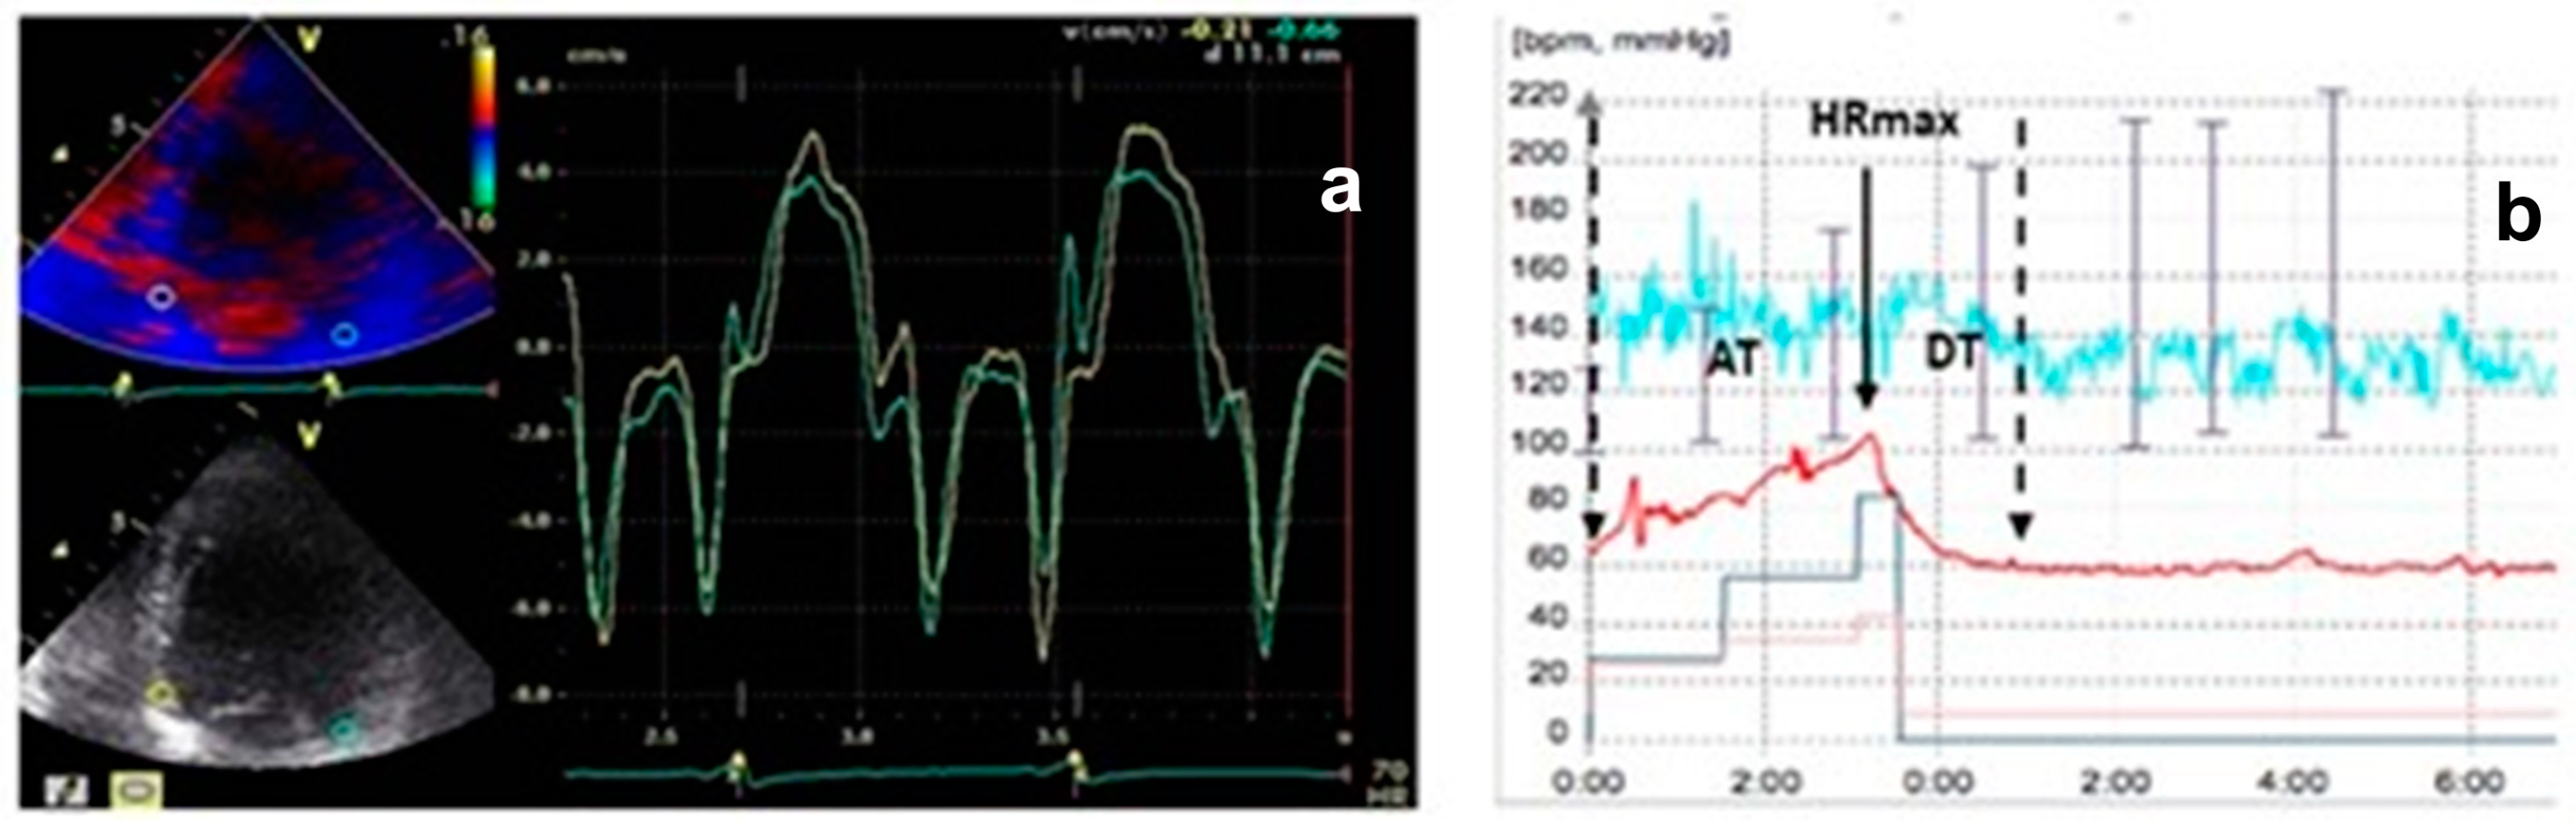

In super-responders, a substantial LV reverse remodeling was observed (LVEDV 193.7 ± 81 vs. 243.2 ± 82 mL at baseline; p < 0.0028), along with reduced LV filling pressures (E/E′ 13.2 ± 4.6 vs. 11.4 ± 4.5; p = 0.0295). These changes correlated with improvements in the resynchronization parameters we studied. The E″T decreased from 90 ± 20 ms to 25 ± 10 ms and was associated with a shorter deceleration time during ET compared to NR (109 ± 68 ms vs. 330 ± 30 ms; p < 0.0001) (Figure 4).

Figure 4.

(a) Super-responders’ TDI pattern; green line = lateral velocity curve; yellow line = septal velocity curve. (b) HRRI diagram in super-responders; red line = heart rate.

An important consideration in our study is the interindividual variability in exercise performance, which may have influenced the HRRI measurements. Despite utilizing the Bruce protocol, patient responses to exercise can differ markedly due to variations in baseline physical conditioning, the presence of comorbidities, and other uncontrolled factors. This variability introduces a potential limitation regarding the reproducibility and consistency of HRRI values. The CRT evaluation during ET encompassed minimum and maximum heart rate, acceleration time (AT), deceleration time (DT), and the AT/DT ratio denoted as the heart rate recovery index (Figure 3).

Graphic representation of the heart rate recovery index (HRRI = AT/DT). B = begin exercise; S = stop exercise; HR = heart rate; HRmax = maximum heart rate; AT = acceleration time; DT = deceleration time (adapted with permission from Cozlac et al. [6]).